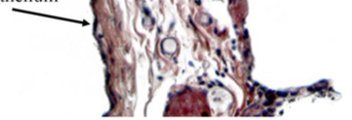

how do you know this is a vocal cord portion of larynx?

what type of region of the larynx is this? how do you know?

transitional.

the epithelium transitions from respiratory to stratified squamous epithelium.

vocal cord

no serous glands

and squamous stratified epithelium